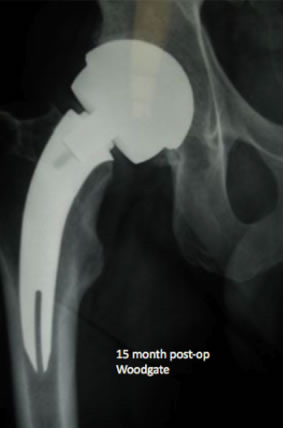

As you can see from this 15 month post-op (now 26 months post-op) there has been visually no changes to x-ray appearance.

Good medial conical flair contact, no distal pedestal, no reactive lines and no apparent medial calcar bone loss.

Note: The lateral cortical neck is retained with the curvature of the stem. This functions like a tension band maintaining strong resistance to both axial and torsional loads. It further provides a physical barrier restricting any potential particulate debris from migrating down the lateral side of the stem.

This curve design also reduces soft tissue injury to the abductors during preparation and stem insertion. |